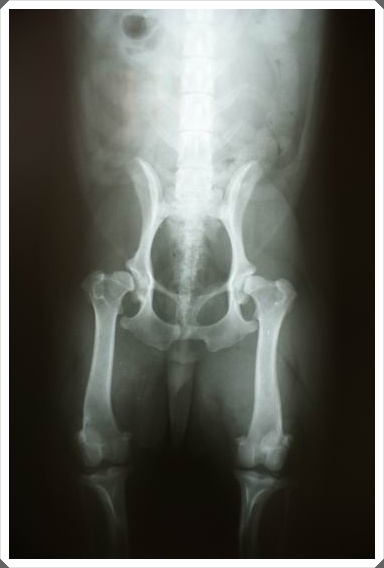

終於緊張的時刻要來到了...共拍了二張x光片...聽說完整的報告會mail到信箱給我...

Dr.李說,從這張x光片看的出來,兩隻腳都有髖關節,

左腳是中度,而右腳因為扭到脫臼,所以已經算是重度了...包覆的沒那麼完整了...